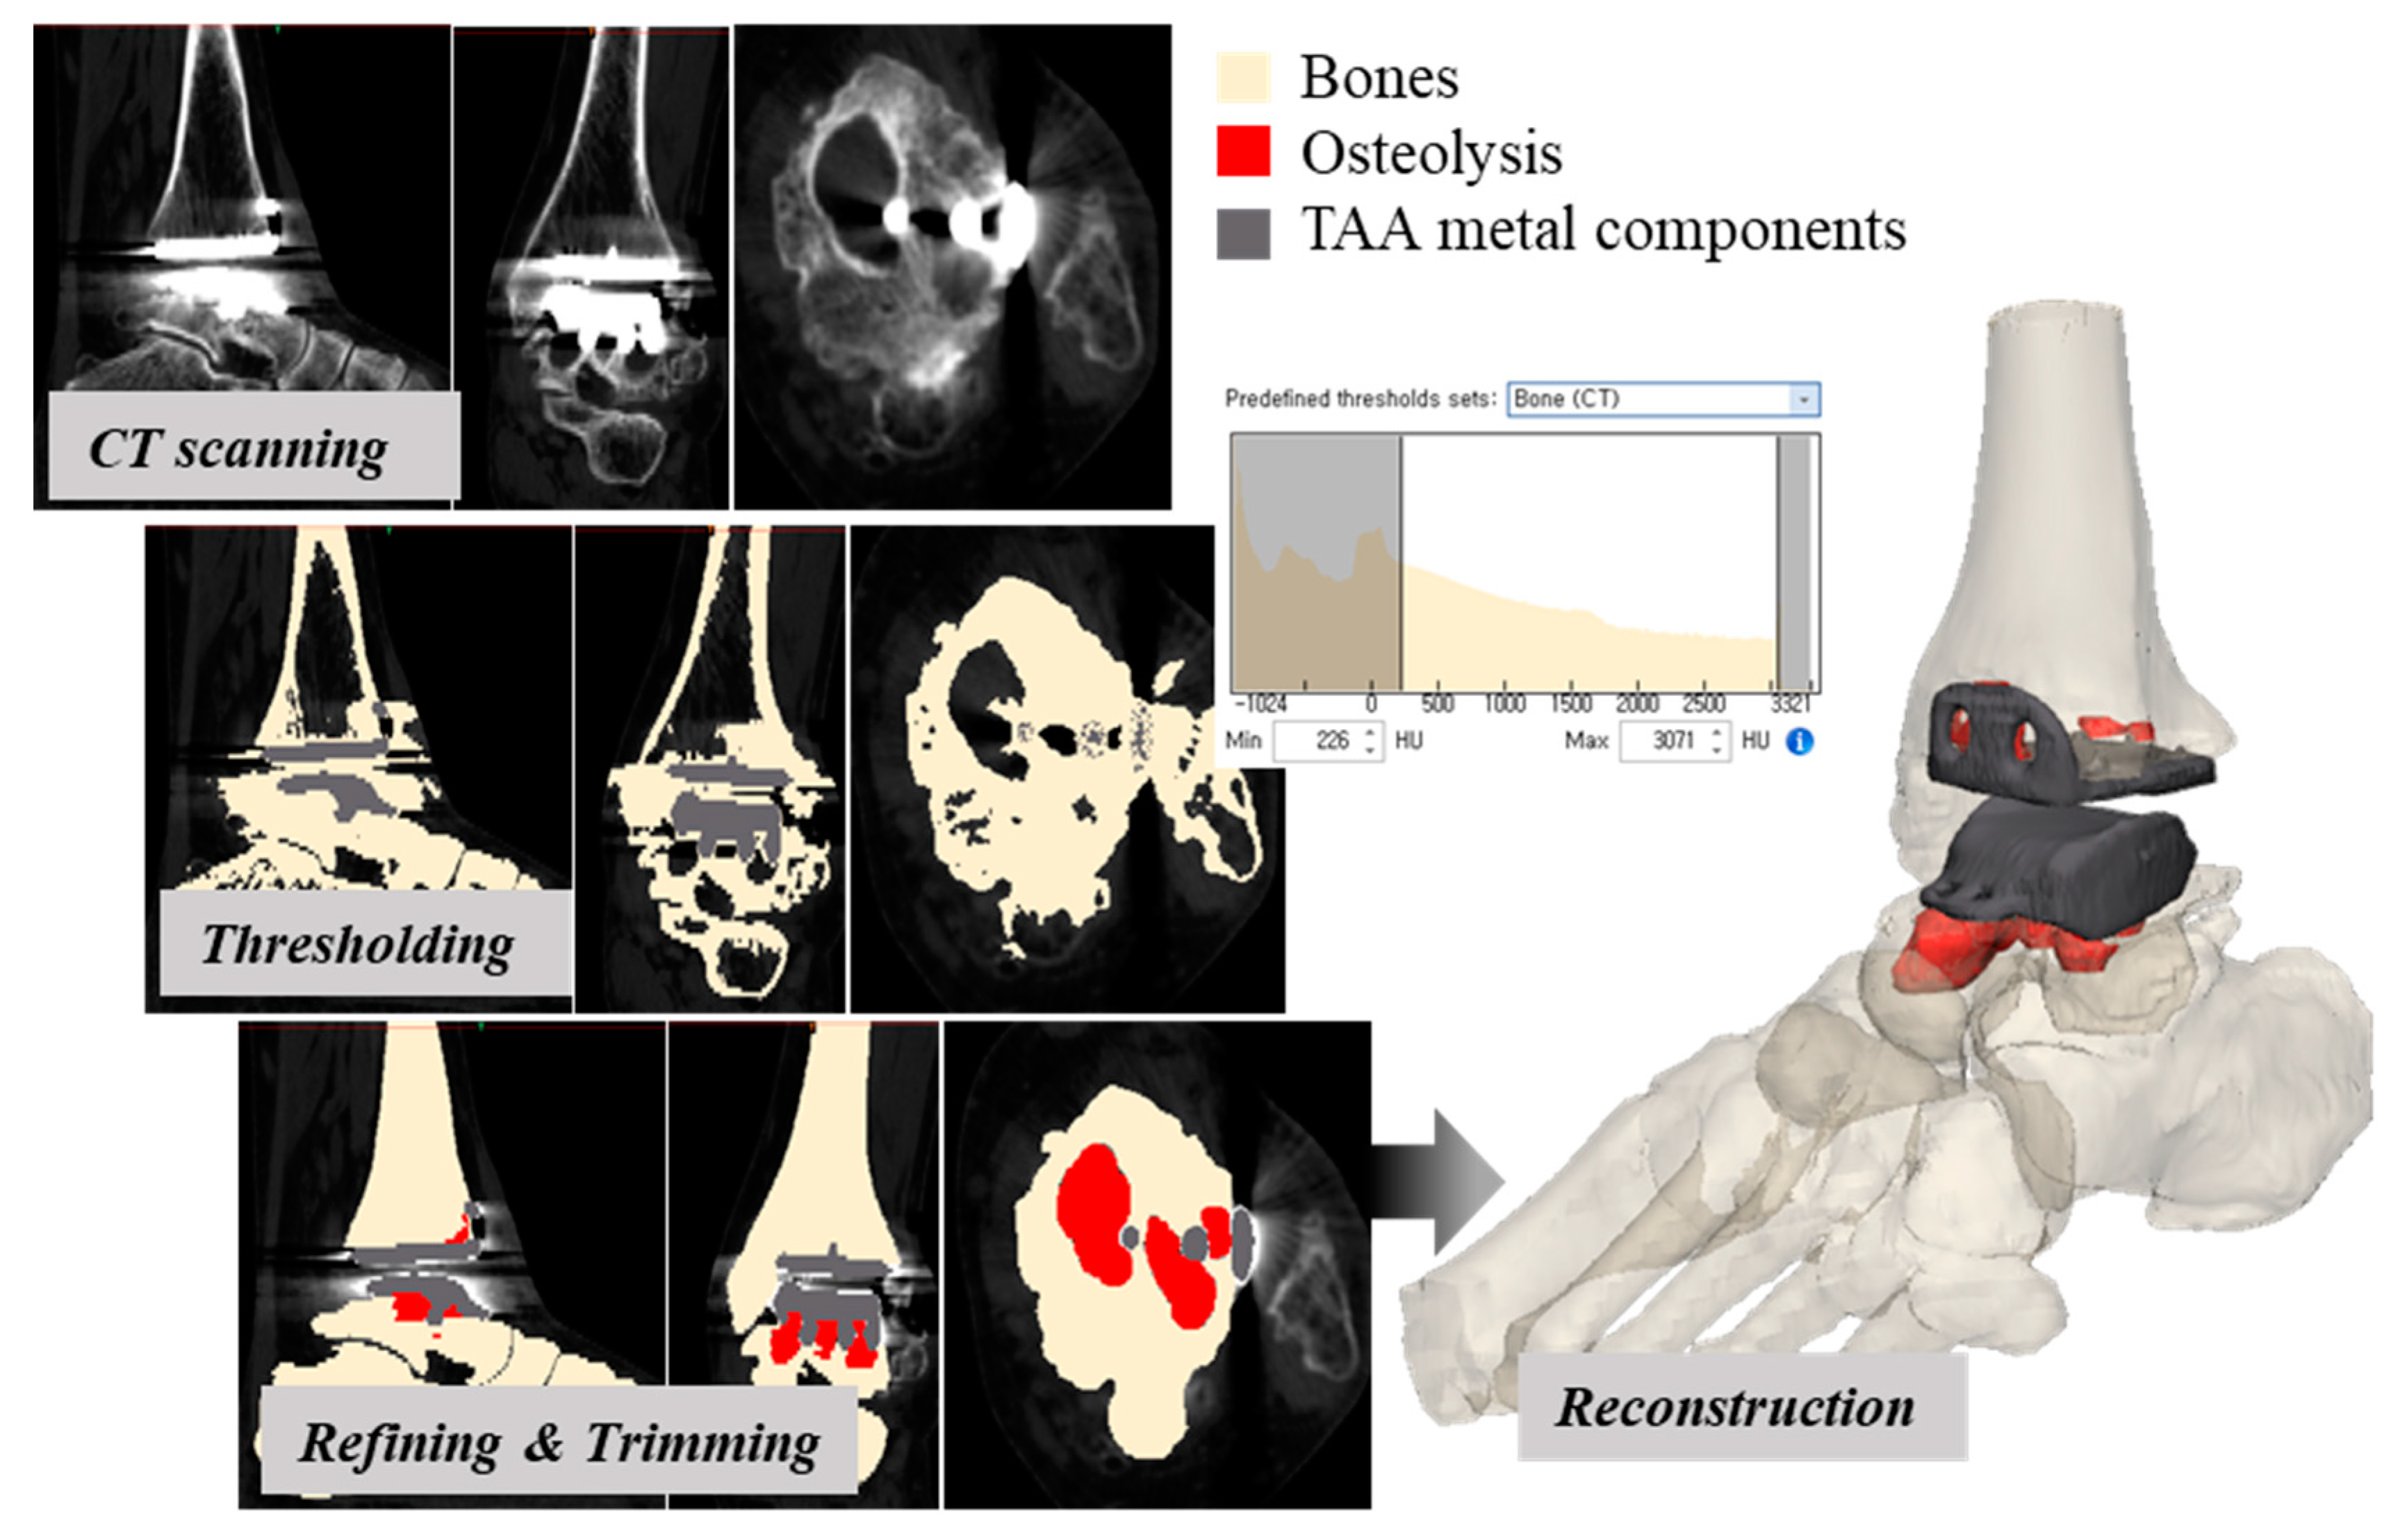

2.2. Computerized Tomography (CT) Scanning and Reconstruction

2.3. Measure of Location, Distribution, and Normalized Volume of Osteolysis